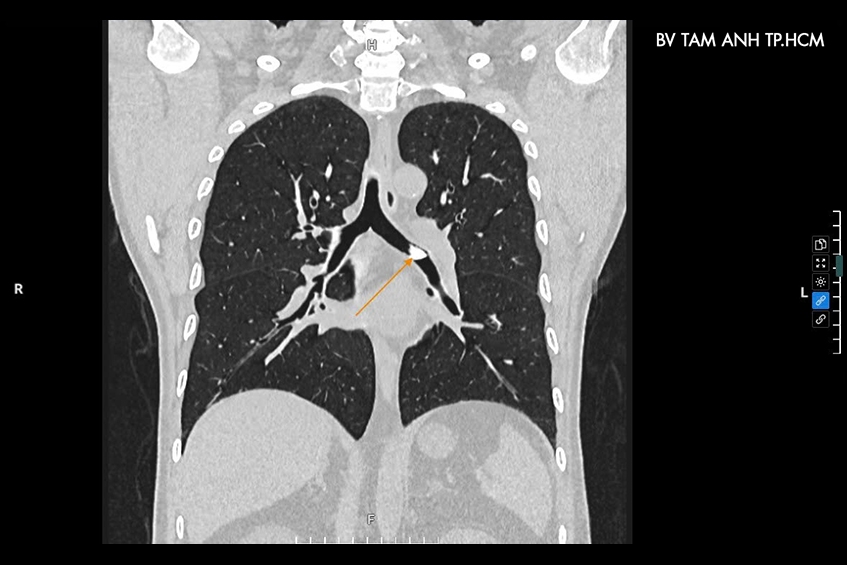

Ngày 16/11, Tiến sĩ bác sĩ Đặng Thị Mai Khuê, Phó khoa Nội tổng hợp, Bệnh viện Đa khoa Tâm Anh TP HCM, cho biết, qua hình ảnh chụp cắt lớp vi tính (CT) lồng ngực 1975 lát cắt phát hiện dị vật hình rẻ quạt, kích thước 2cm, ghim trong lòng phế quản chính bên trái, gây tắc hẹp lòng phế quản. Đây chính là nguyên nhân khiến đường dẫn khí từ khí quản vào phổi bị cản trở gây khó thở, đau ngực, ho khan kéo dài ở người bệnh.

Khi có triệu chứng hoặc nghi ngờ hóc dị vật trong đường thở, người bệnh nên thăm khám kịp thời tại chuyên khoa hô hấp hoặc nội tổng hợp có đầy đủ thiết bị y tế chuyên dụng. Nếu có yếu tố nghi ngờ mắc dị vật, bác sĩ sẽ chỉ định chụp X-quang ngực hoặc CT phổi giúp chẩn đoán, phát hiện kịp thời các dị vật, từ đó có biện pháp can thiệp lấy dị vật ra ngoài an toàn, tránh để lâu gây biến chứng nguy hiểm.